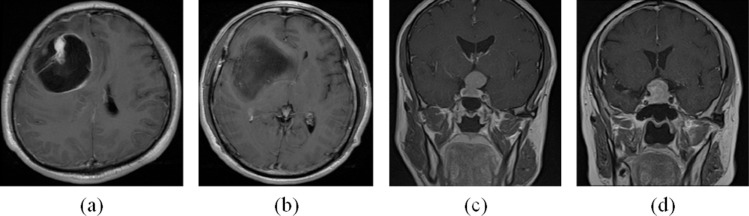

脑肿瘤术前分类是制定个性化治疗方案的关键,但现有的分类方法依赖于人工干预,往往存在效率和准确性方面的问题,在临床实践中可能导致误诊或延误诊断,影响治疗效果。提出了一种全自动脑肿瘤磁共振成像(MRI)分类方法,该方法由基于改进U-Net的特征提取器和基于卷积递归神经网络(CRNN)的分类器组成。基于密集块的特征提取器的编码器增强了特征的传播,减少了参数的数量。该解码器利用残差块来降低部分特征的权重,以提高MRI空间序列重构的效果,避免梯度消失。编码器和解码器之间的跳过连接有效地合并低级特征和高级特征。将提取的特征序列输入到基于crnn的分类器中进行最终分类。我们评估了胶质瘤分级、胶质瘤异酸脱氢酶1 (IDH1)突变状态分类和垂体瘤质地分类的方法在两个数据集上的性能,一个是当地附属医院收集的胶质瘤或垂体肿瘤,另一个是来自TCIA的胶质瘤成像数据。与常用模型和新模型相比,我们的模型准确率更高,准确率为90.72%,对胶质瘤IDH1突变状态的分类准确率为94.35%,对垂体肿瘤纹理的分类准确率为94.64%。

Preoperative classification of brain tumors is critical to developing personalized treatment plans, however existing classification methods rely on manual intervention and often have problems with efficiency and accuracy, which may lead to misdiagnosis or delayed diagnosis in clinical practice and affect the therapeutic effect. We propose a fully automated approach to brain tumor magnetic resonance imaging (MRI) classification, consisted by a feature extractor based on the improved U-Net and a classifier based on convolutional recurrent neural network (CRNN). The encoder of the feature extractor based on dense block, is used to enhance feature propagation and reduce the number of parameters. The decoder uses residual block to reduce the weight of some features for improving the effect of MRI spatial sequence reconstruction, and avoid gradient disappearance. Skip connections between the encoder and the decoder effectively merge low-level features and high-level features. The extract feature sequence is input into the CRNN-based classifier for final classification. We assessed the performance of our method for grading glioma, glioma isocitrate dehydrogenase1 (IDH1) mutation status classification and pituitary tumor texture classification on two datasets, glioma or pituitary tumors collected in a local affiliated hospital and glioma imaging data from TCIA. Compared with commonly models and new models, our model achieves higher accuracy, with an accuracy of 90.72%, classified glioma IDH1 mutation status with an accuracy of 94.35%, and classified pituitary tumor texture with an accuracy of 94.64%.